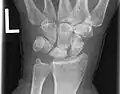

Radiographic classification

First described by David Lichtman et al. in 1977.[7] The purpose of this classification system is to guide treatment and to enable comparison of clinical outcomes.

1. Stage I Normal radiograph (possible lunate fracture).

2. Stage II Sclerosis of the lunate without collapse. (Portions of the lunate begin to deteriorate. This shows as a white blemish on x-rays.)

3. Stage IIIA Lunate collapse and fragmentation, in addition to proximal migration of the capitate.

4. Stage IIIB Lunate collapse and fragmentation, in addition to proximal migration of the capitate. In addition there is fixed flexion deformity of the scaphoid.

5. Stage IV Changes up to and including fragmentation, with radiocarpal and midcarpal arthritic changes.

Negative ulnar variance.